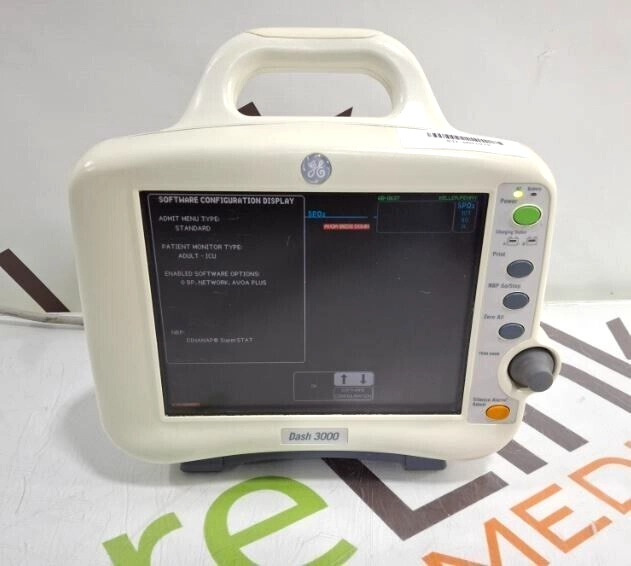

GE Healthcare Dash 3000 - Masimo SpO2 Patient Moni

$93.00

USD

GE Healthcare Dash 3000 - Masimo SpO2 Patient Moni

$93.00

USD

GE Healthcare Dash 3000 - GE/Nellcor SpO2 Patient

$62.00

USD

GE Healthcare Dash 3000 - GE/Nellcor SpO2 Patient

$62.00

USD

GE Dash 3000

$1,795.00

USD

GE Dash 3000

$1,795.00